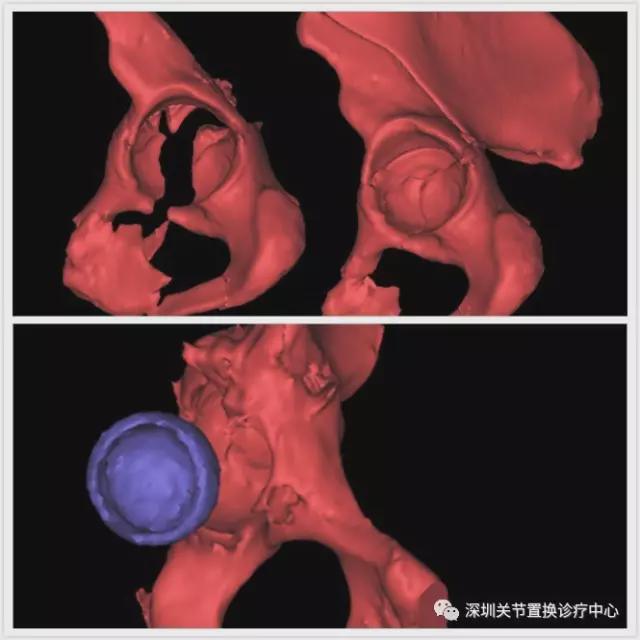

术前3D打印髋关节,以设计髋臼侧手术方案

千疮百孔的髋臼,怎么才能把人工髋臼牢牢的放进去呢?

按照3D打印制作的骨板,以修补髋臼缘